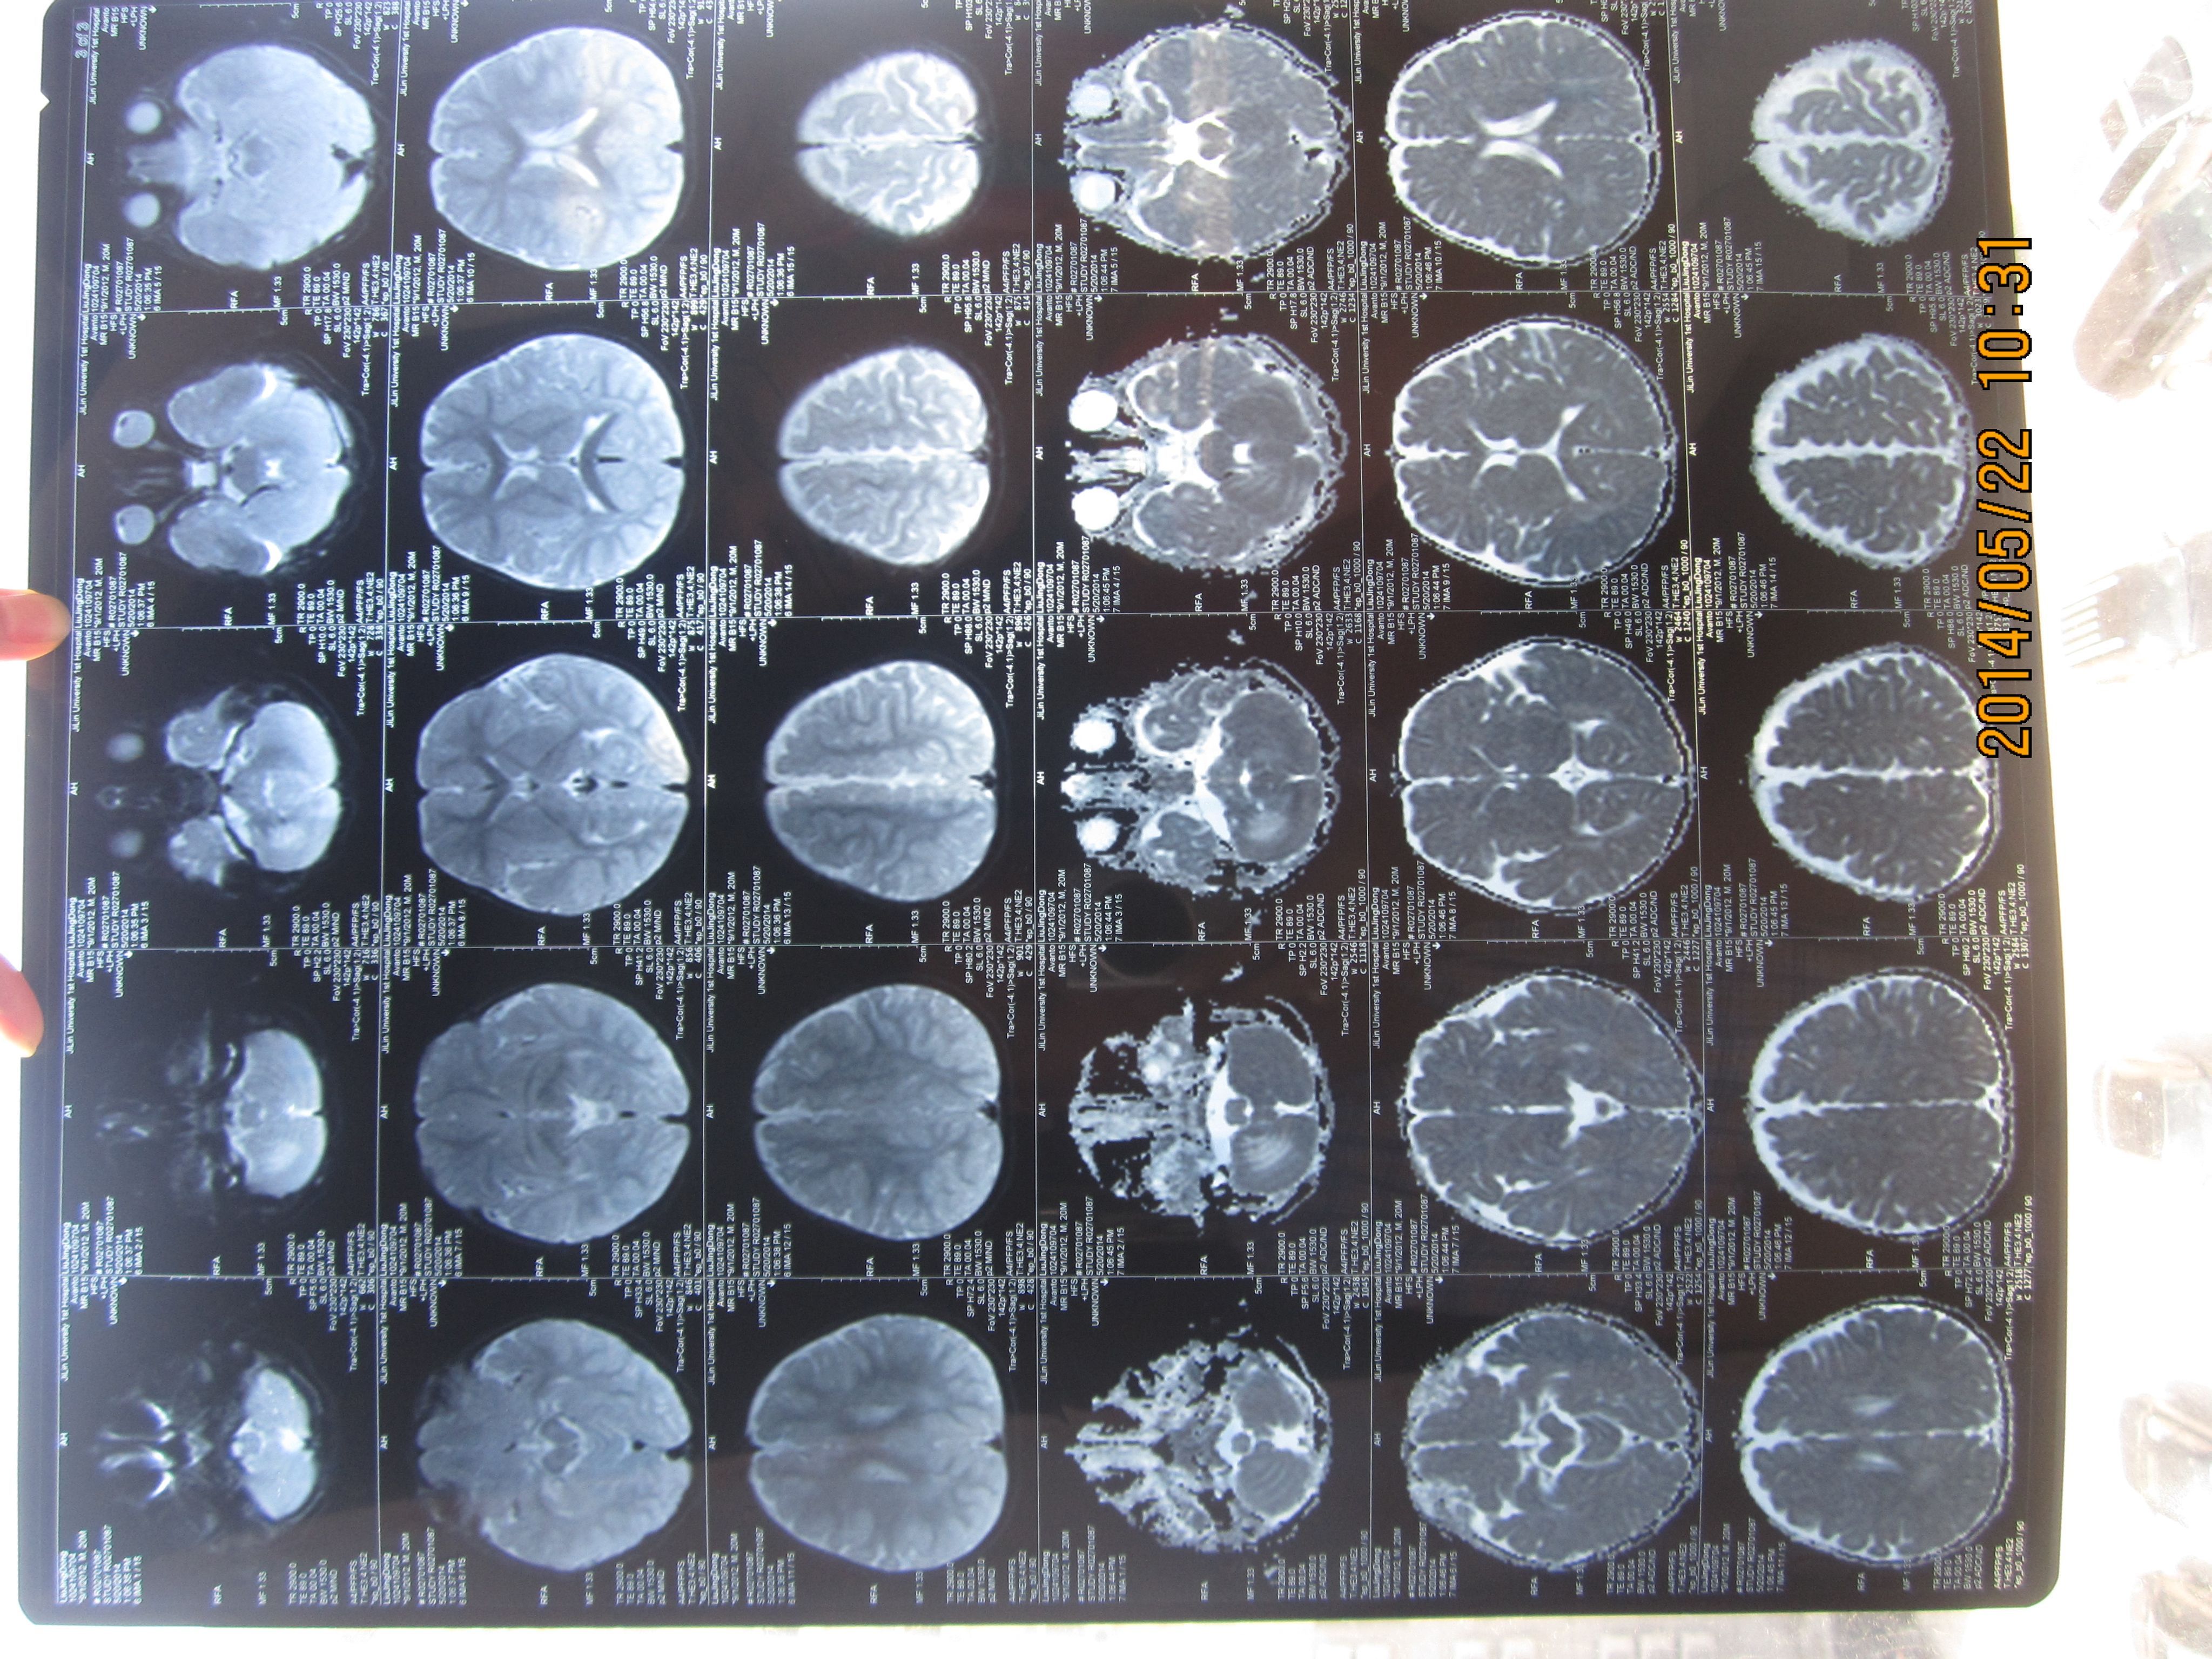

孩子8个月时做了核磁,医生说是小脑血管瘤 20个月时,小孩晚上睡了一觉醒来,右脚没劲,不能行走(孩 子一直走路不好,但也能走3米左右),做完核磁,医生诊断为突发性小脑炎。距发现孩子不能走三天后,孩子的脚慢慢恢复了正常,期间未做任何治疗。想知道孩子究竟小脑里怎么了,是什么病,上哪儿能治疗? 点击展开 匿名用户 2014-05-22 11:07 为您推荐: 其他回答 病情分析: 您的情况考虑是血管瘤, 指导意见: 一般来说是良性,生长缓慢,很少恶变。可用冷冻疗法或手术切除,也可用X线照射治疗。 种凌丝_IyuJ 2014-05-22 12:04 相关问题 小孩下肢痛,彩超,及核磁显示,血管畸形,说是血管瘤,问有什么好的治疗方法吗? 核磁能诊断肝血管瘤还是肝癌吗,1CM大小 核磁发现腰1椎体血管瘤,骶2有个囊肿